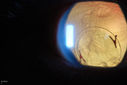

Free Floating Dislocated Lens in Vitreous505 viewsPatient comes in aphakic with dislocated lens floating to the back of the eye when laying down. Lens is laying up against the endothelium of the cornea when patient is right side up..00000